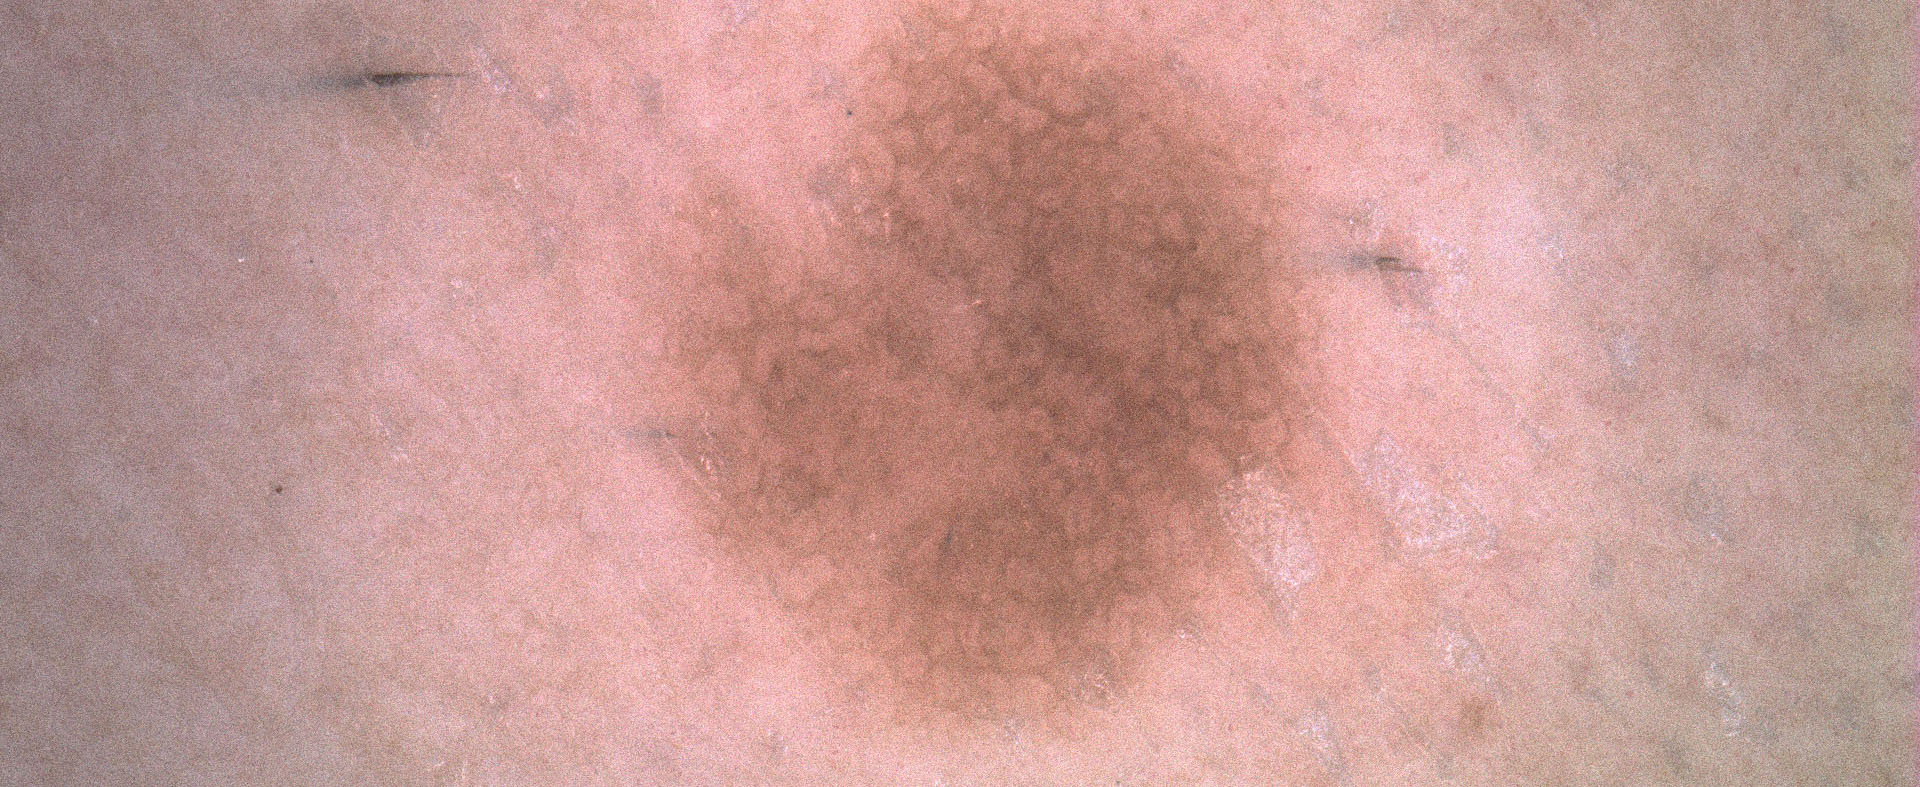

Color balance

A volte osservare le immagini dermoscopiche con una luce differente aiuta a scoprire piccoli dettagli che possono essere vitali nei processi diagnostici.

La funzione di Color Balance del software di IRSKIN professional è uno strumento algoritmico standard che bilancia le intensità di colore delle immagini acquisite.

Poiché modifica le immagini, può essere utilizzato solo nella fase di visualizzazione, semplicemente spuntando la casella Color Balance.

Prima di usare

color balance

Dopo aver usato

color balance